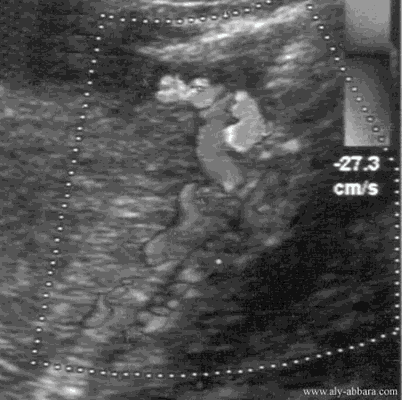

Artère utérine parcourant le bord latéral de l'utérus (une femme enceinte de 23 SA).

On observe bien sa forme spiralée lui permettant son extension en longueur fur et à mesure de l'extension volumique de l'utérus au cours de l'évolution de la grossesse.